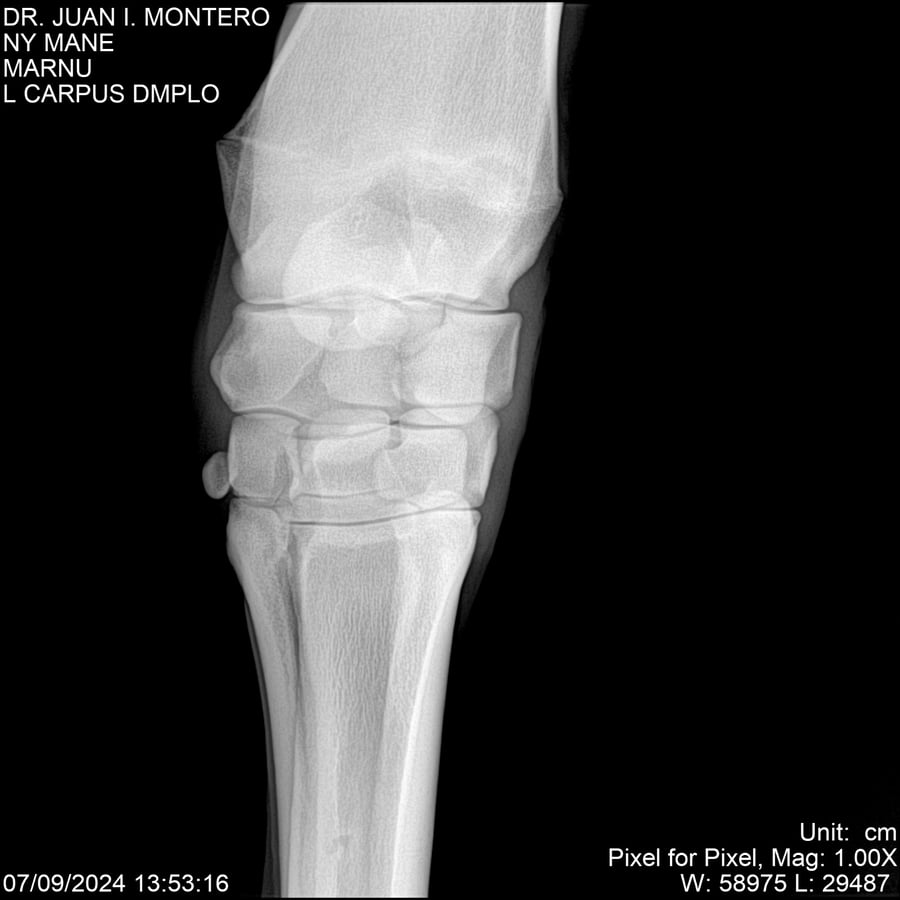

LOTE 20, NY MANE Lote Anterior Volver al remate Lote Siguiente Ficha Contacto Montevideo - Ficha del Lote Identificador: #282520 Categoría: Yeguarizos 76 Visualizaciones ClicData Contacto Empresa: Abelenda N. R., Walter Hugo Nombre*: Teléfono* : E-mail* : Mensaje Enviar Registrese gratis Este contenido Exclusivo está disponible sólo para usuarios registrados Ingresar